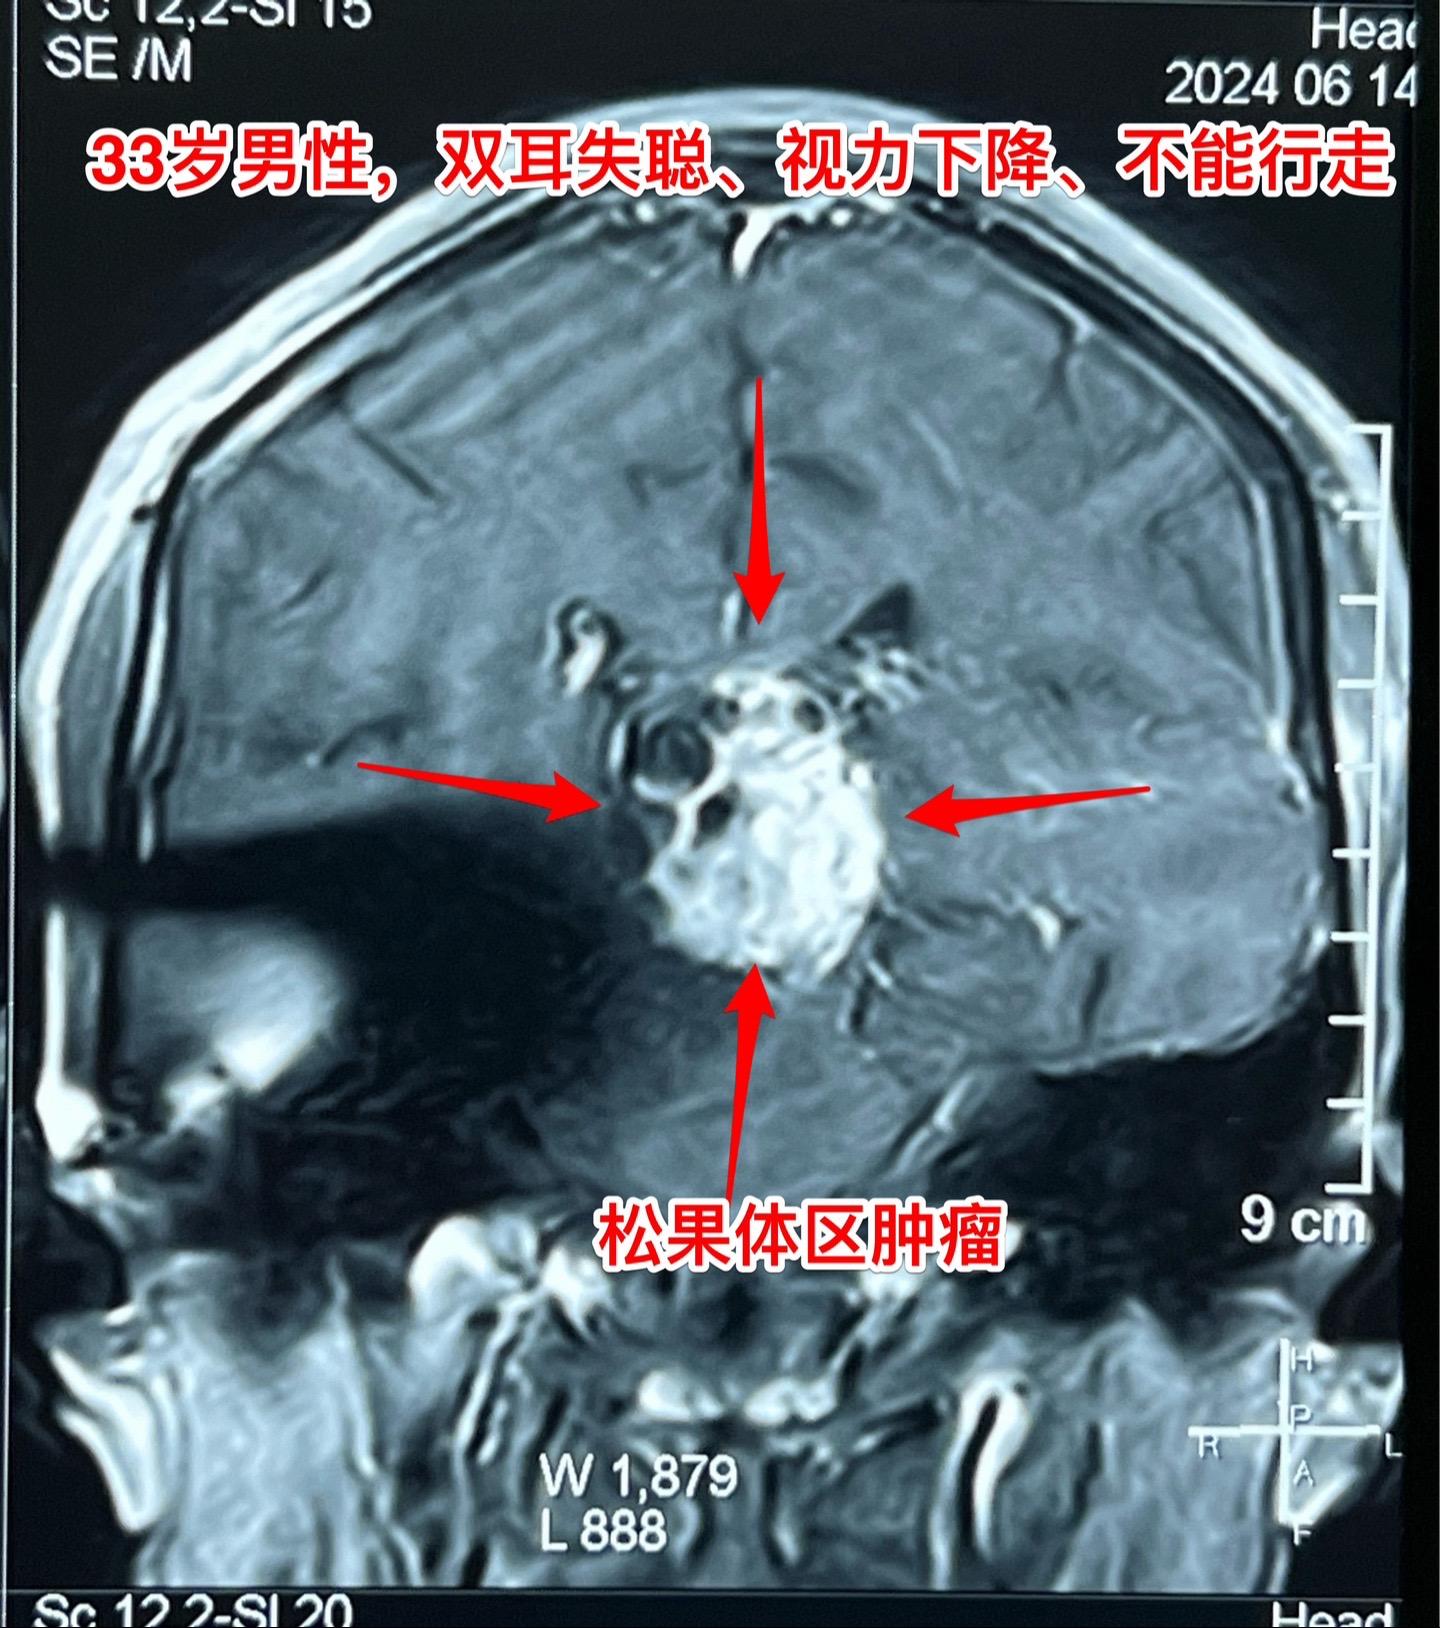

33岁贵州男性,脑部畸胎瘤。33岁贵州男性,病史11年。 11年前因多饮多尿在北京市某医院按生殖细胞瘤行全脑放疗,之后症状好转,能工作。 近两个月他记忆力差、爱睡觉、听力下降、视力下降。脑部磁共振显示松果体区肿瘤,在北京市某医院行肿瘤穿刺活检术,病理报告结果考虑是乳头型颅咽管瘤(活检标本标注为鞍区占位,可能误导了病理科医生,见图6)。 放疗医生及化疗医生说根据这个病理 结果是不敢实施放疗和化疗的。神经外科医生说开颅切除肿瘤风险非常大。 处于绝